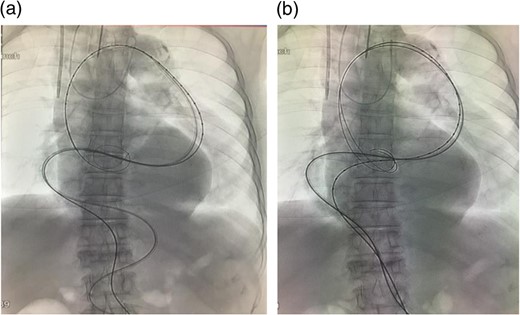

The stent graft (Relay Plus® 38 × 34 × 200 mm, Bolton medical, Barcelona) was introduced through the right common femoral artery. When it reached the distal site of the thoracoabdominal aorta where the angulation was the most severe, the outer hard sheath was left there while the inner flexible sheath was advanced. The flexible sheath was successfully introduced to the proximal site of the thoracoabdominal aorta beyond the angulation (Fig. 3). The stent graft was placed and we confirmed that no endoleak existed (Fig. 4).

Angiographic image at the completion of treatment. No endoleak was observed. There was no contrast enhancement in the location of the aneurysm.